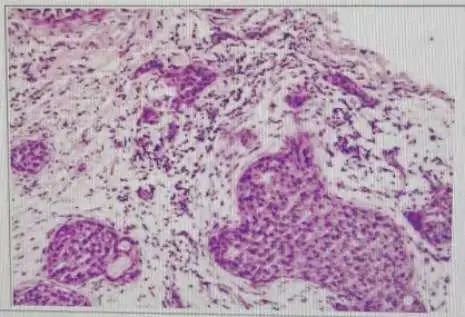

病理活检

图片来源:肖伟锴医生提供这个是最终的确诊手段,只有病理确诊了才算是真正确诊乳腺癌了。

最常用的是穿刺活检(类似打针),需要在超声或者其他手段的引导下,穿刺约 3 小条组织(类似 1 厘米的粉丝)送去病理科化验,病理科医生对组织染色以后运用显微镜看病变组织里面有无癌细胞,如果看到癌细胞则确诊为癌。

其他活检手段还包括微创旋切(切取的肿块较大)或者开放手术(切除整个肿块)送去病理科化验。